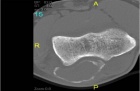

20 year old female who two months prior sustained a fall on to her right outstretched upper extremity and sustained an olecranon fracture for which she has undergone nonoperative management. She recalls that she had been experiencing discomfort in the right elbow prior to sustaining her injury.